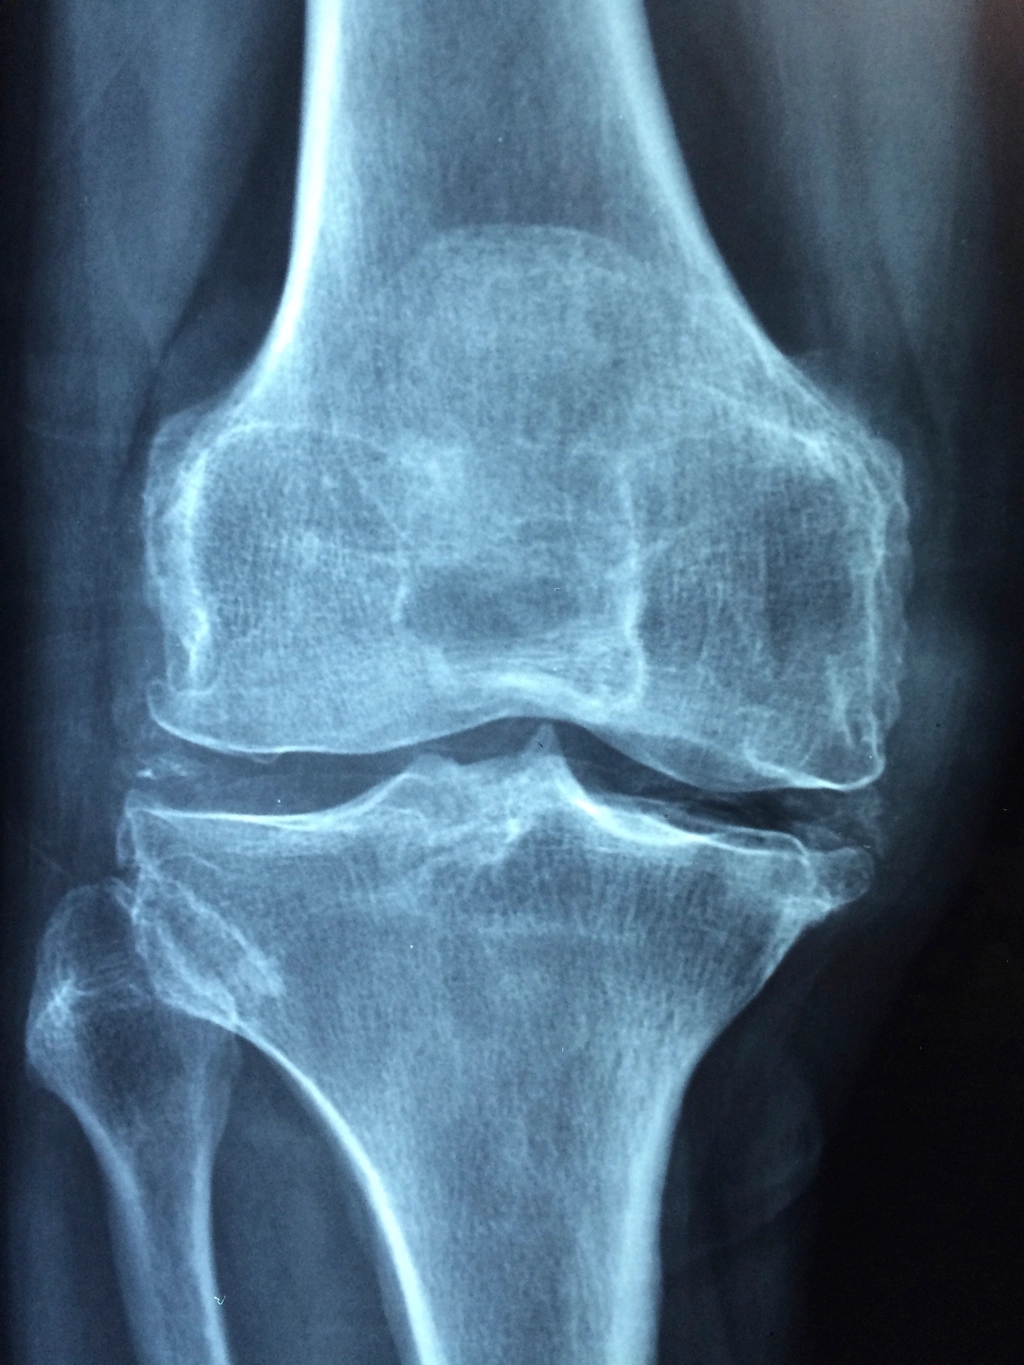

Knee and Hip Osteoarthritis: Does Train Assist or Harm?

Therapeutic train helps a bit of. However don’t anticipate a dramatic enchancment, in line with this 2023 examine printed at The Lancet Rheumatology. The advantages are inclined to accrue to sufferers who’re in most ache and most bodily impaired at baseline.